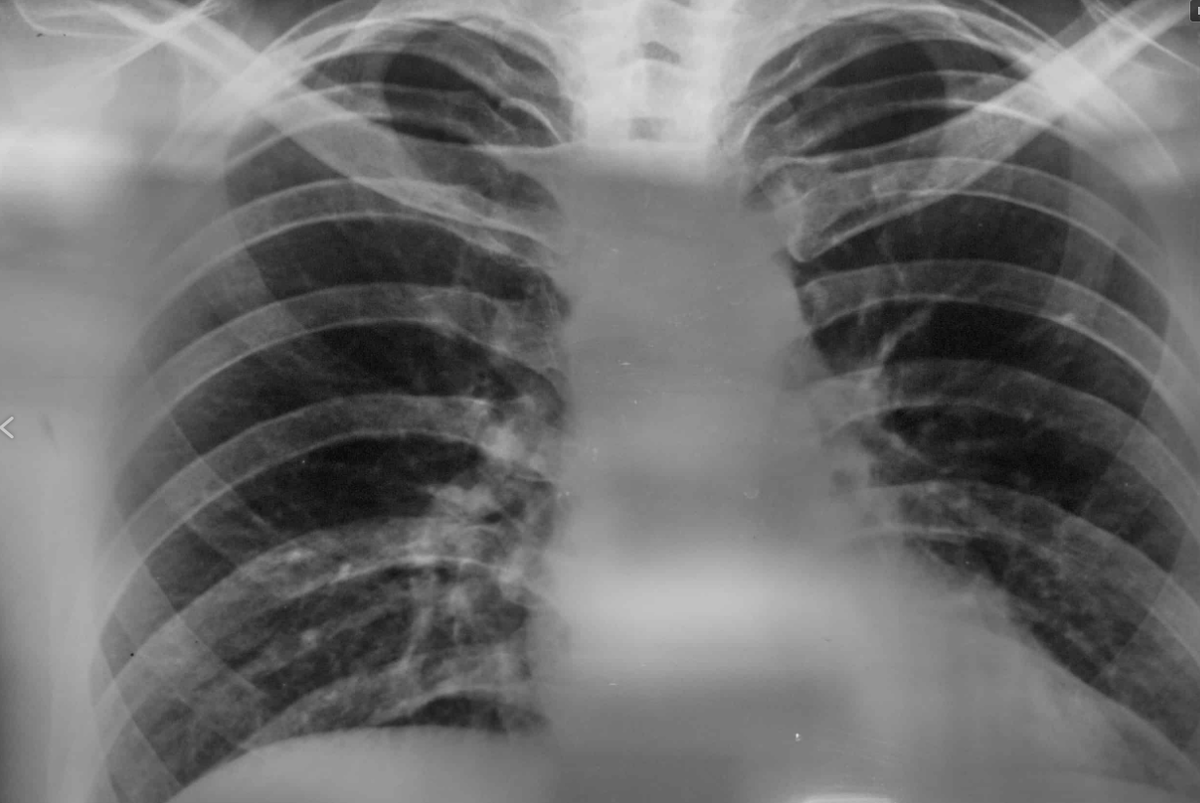

Итак, что же за бронхит был вылечен одним махом? Пожилая женщина кашляла в течение четырех лет. Кашель был сухой, неприятный, возникал преимущественно вечером и ночью и мешал спать. Мокрота не откашливалась. Рентген органов грудной клетки, который выполнила пациентка, был описан довольно аморфно, но таким образом, что врачи, смотревшие заключение, находили в нем подтверждение версии о бронхите. Зачем-то назначали муколитики, призванные делать мокроту менее вязкой. Но мокроты так и не появилось. К счастью, до назначения антибиотиков дело не доходило, иначе бы еще и кишечный микробиом мог бы пострадать.